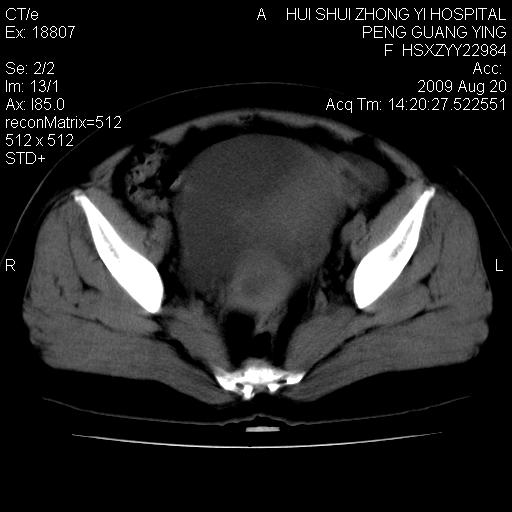

标题: CT21707:女,42岁,因发现下腹部包块2月。 [打印本页]

标题: CT21707:女,42岁,因发现下腹部包块2月。

软组织密度,与子宫一致。双侧卵巢形态、密度好,不支持来源于卵巢。

来源卵巢--畸胎类肿瘤

病史不全面,病灶来源可能是子宫或卵巢,若临床有剖腹产、痛经史,则更支持前者,亦更支持子宫腺肌症